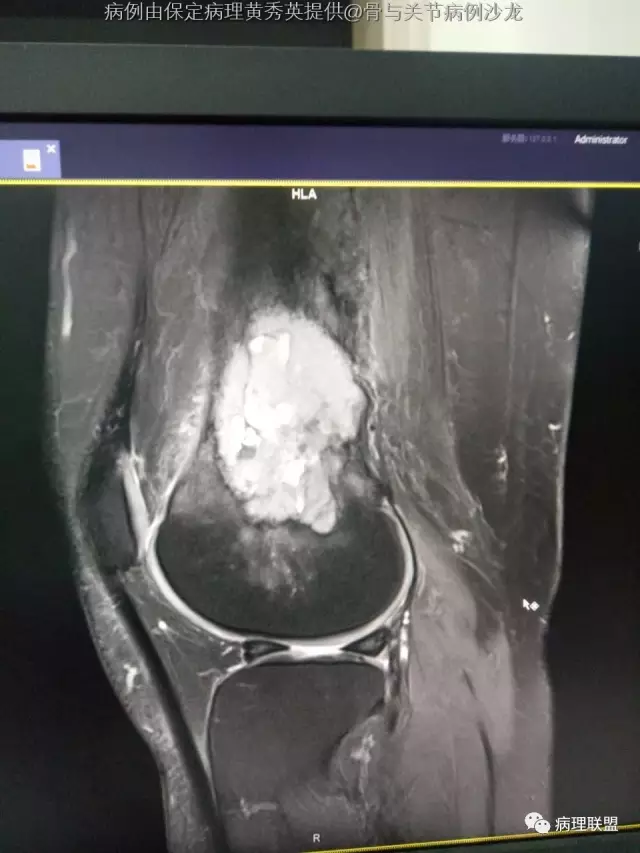

女67岁,股骨下端肿物约6cm,(病例由保定病理黄秀英提供,致谢!)